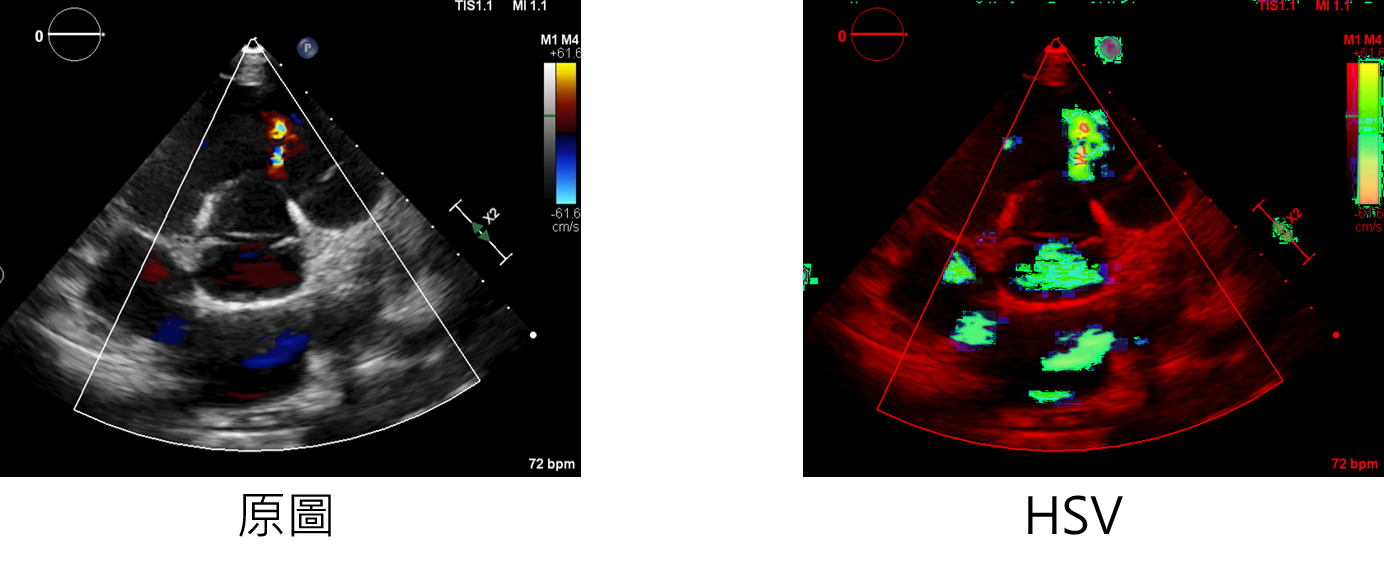

參數說明

HSVcolor:增強方法

輸入範例:

datagen=CustomDataGenerator(fun="HSVcolor",dtype=int)